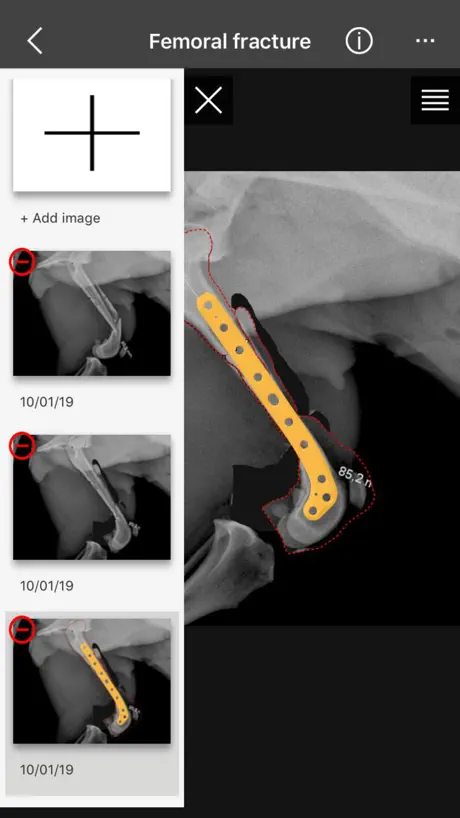

Following our service of direct technical assistance between our biomedical engineers and the surgeon, the BETA app is the digital planning solution development for planning your trauma and orthopaedic procedures with BETA implants: BETA app.

6. Save in project

Following our service of direct technical assistance between our biomedical engineers and the surgeon, the BETA app is the digital planning solution development for planning your trauma and orthopaedic procedures with BETA implants: BETA app.

6. Save in project